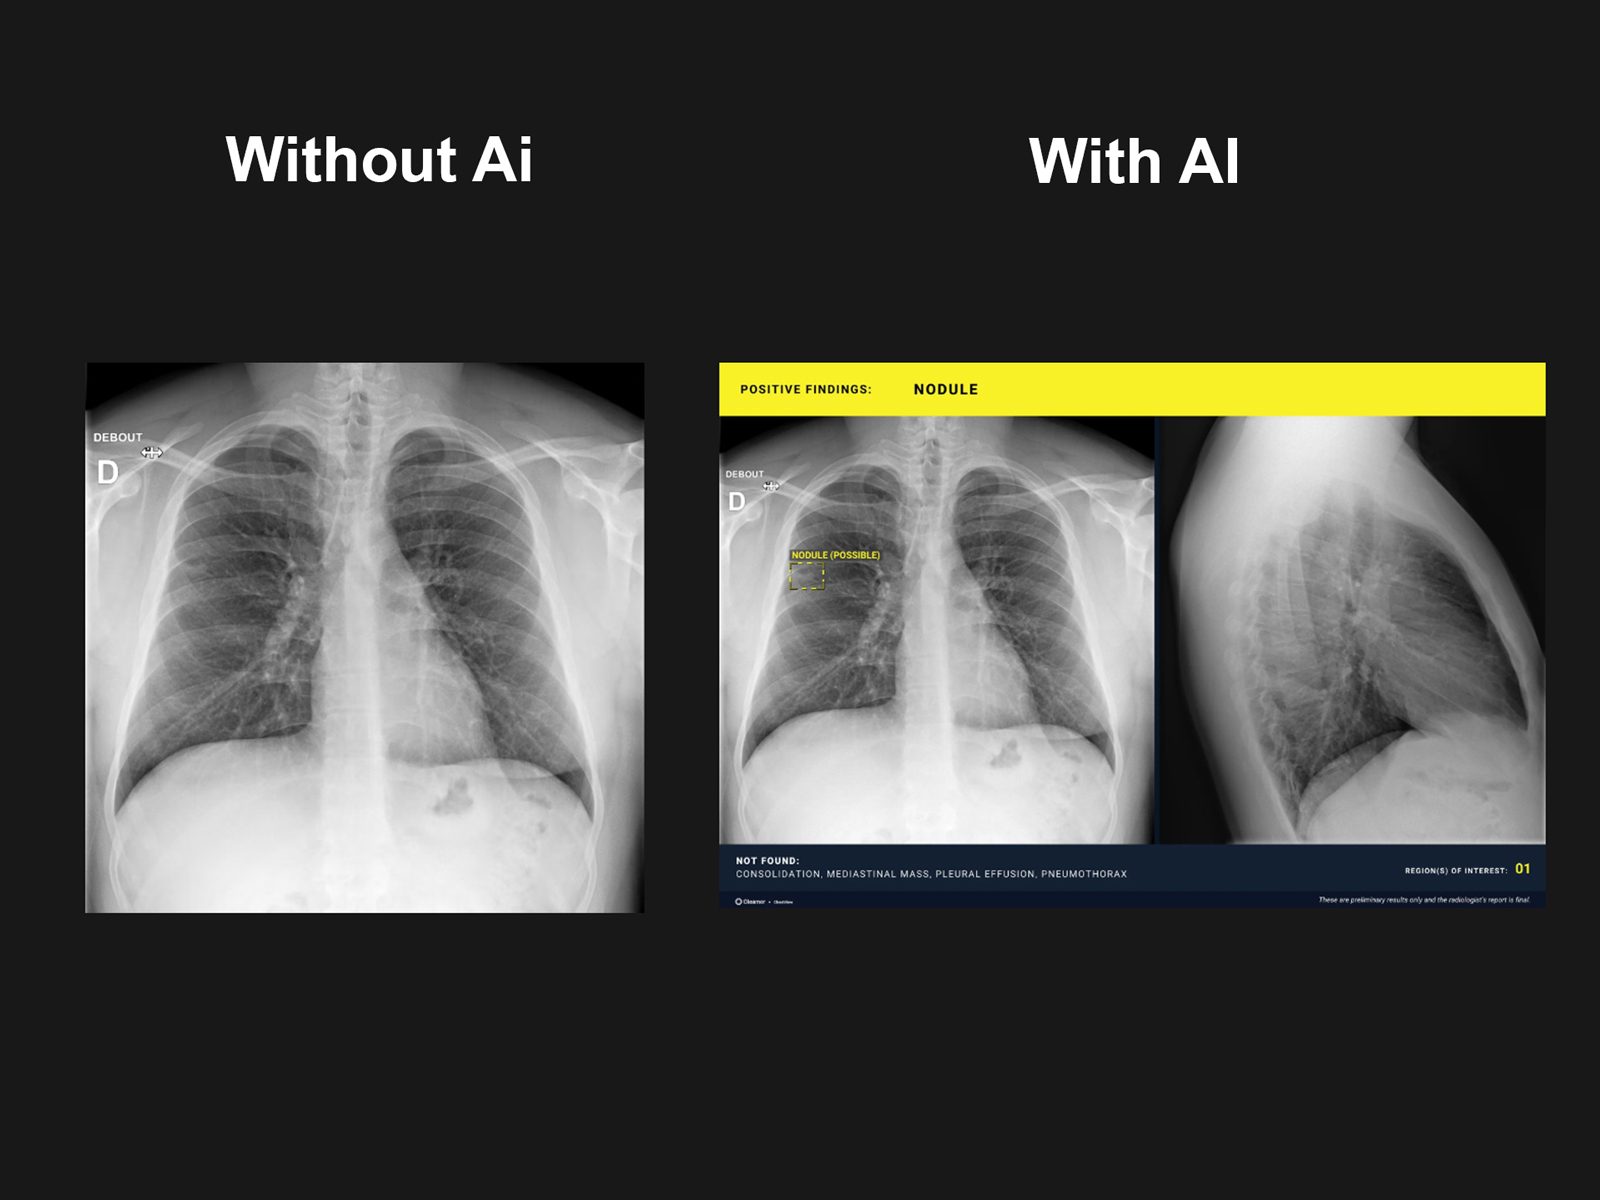

• Radiografia cu overlay, ce include markeri si denumiri ale patologiilor detectate, dupa cum vor fi descrise mai jos

• Zone suspecte marcate prin contur „bounding-box”

• Marcaje cu denumire pentru multiple leziuni (pneumonii, pneumotorax, noduli pulmonari, mase suspecte)

• Numar regiuni de interes

• Anomalii identificate (pozitive findings) vs anomalii neidentificate in studiu (negative findings)